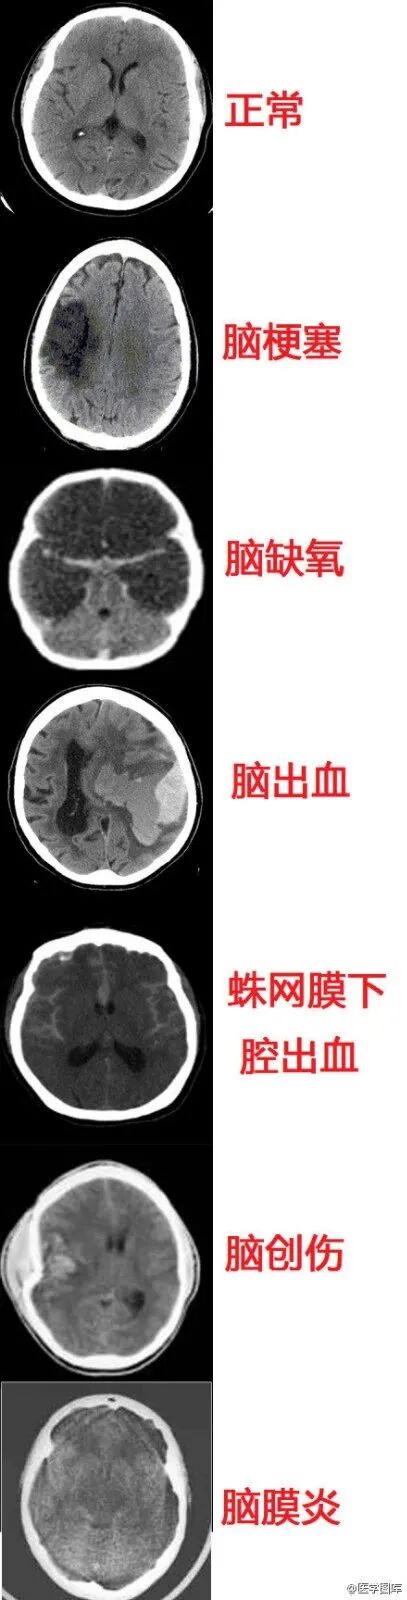

6.几种常见致死性脑病的CT表现